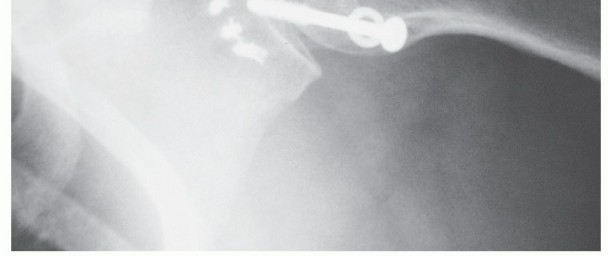

FIG 4 • A. AP radiograph of the right shoulder in a patient with previous Magnuson-Stack procedure (the subscapularis tendon has been stapled laterally to the bicipital groove). B. AP radiograph of the right shoulder in a patient with a Latarjet procedure. There are two screws securing the coracoid bone block to the glenoid.*

The Magnuson-Stack procedure is a transfer of the subscapularis tendon lateral to the bicipital groove (FIG 4A).

The Latarjet procedure lays the coracoid on its side, parallel to the glenoid face, and is typically secured with two screws (FIG 4B).

Although several authors have achieved excellent success with these procedures, the concern for hardware migration and late resorption of the bone block have made these procedures less popular than the anatomic procedures. They are used mainly for revision procedures and in cases where there is deficient glenoid bone stock.